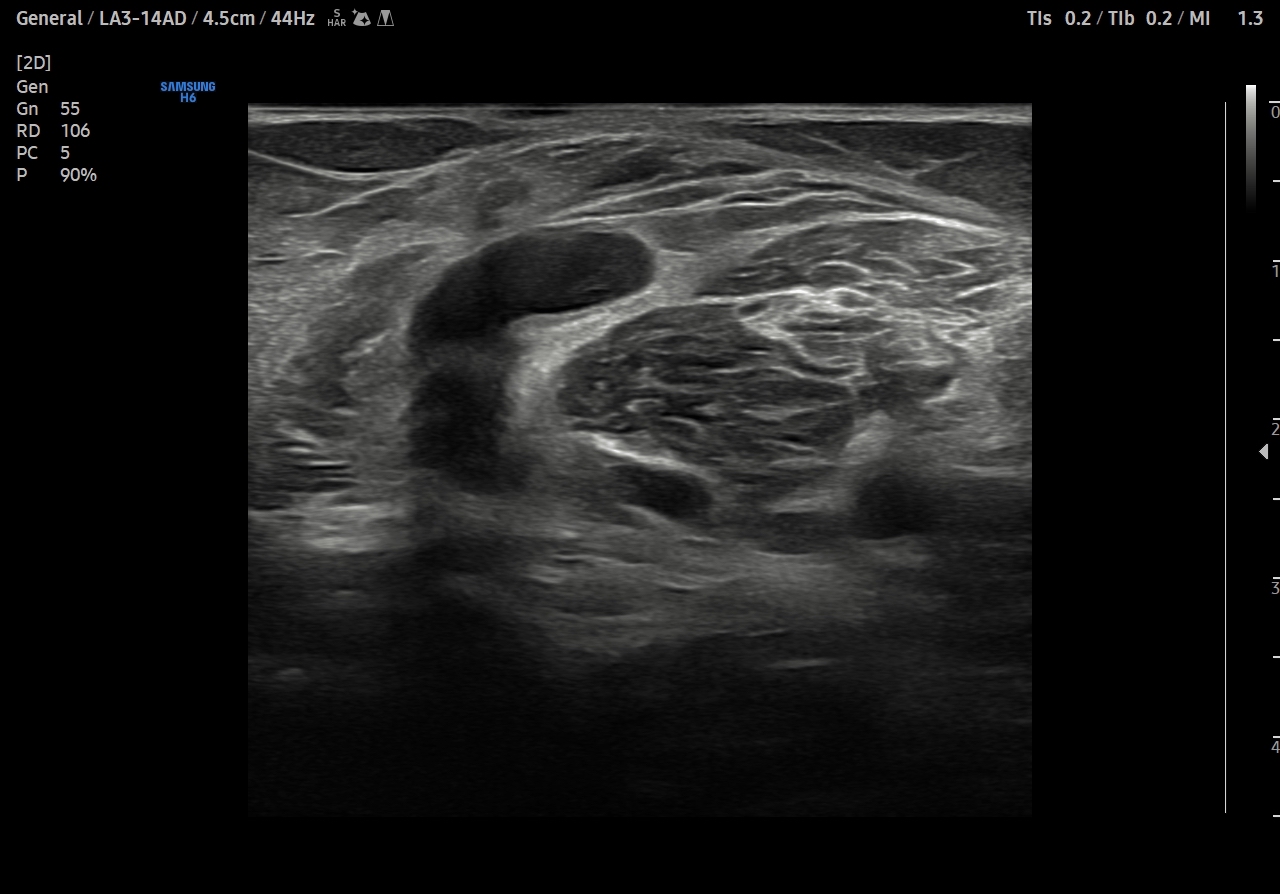

Descripción de los hallazgos ecográficos y las imágenes más relevantes para la resolución del caso

Se explora cara anterior, lateral y medial de rodilla sin hallazgos significativos. En cara posterior se explora el hueco poplíteo donde se visualiza en corte transversal una estructura hipoecoica con la base, el cuello entre el tendón del semimembranoso y el tendón de la cabeza medial del gemelo interno y el cuerpo. Sin signos de complicación. Permeabilidad del sistema venoso profundo.